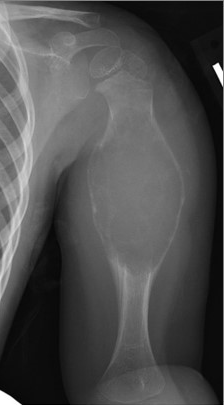

- Το βραχιόνιο οστό (το μακρύ οστό στο χέρι που εκτείνεται από τον ώμο μέχρι τον αγκώνα)

Αναπαραγωγή από LeeDH, Hills, JM, JordanovMI, Jaffe, KA: Κοινοί Όγκοι και Όγκοι-Μοιες Βλάβες του Ώμου. JAmAcadOrthopSurg 2019; 27(7):236-245.

Ακτινογραφίες. Ο γιατρός σας ή ο γιατρός του παιδιού σας πιθανότατα θα παραγγείλει ακτινογραφίες για να εξετάσει το υποκείμενο οστό.

Η ακτινογραφία συνήθως δείχνει μια οστική βλάβη που έχει αλλάξει το σχήμα και την αντοχή του οστού. Συνήθως, το οστό είναι διευρυμένο με ένα καθαρό κενό στη μέση και ο φλοιός του οστού (ισχυρό εξωτερικό στρώμα) είναι λεπτός.